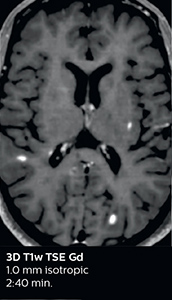

Ingenia Elition 3.0T with Compressed SENSE

3D FLAIR 1.0 x 1.0 x 1.0 mm* 2:50 min.

3D TSE T1w 1.0 x 1.0 x 1.0 mm* 2:10 min.

The abbreviated MS protocol for brain is only around 9 minutes, so in case of suspected multiple sclerosis, one or two more advanced sequences may be added, such as PSIR (phase sensitive inversion recovery) or susceptibility-weighted sequences to help us make more confident diagnoses in these inflammatory cases.

In this example, the optional 3D multishot susceptibility weighted sequence with 0.6 mm isotropic voxels is 2 lesions with a central vein sign (arrows) and one lesion with a phase-rim sign (arrowhead). The total scan time, including SmartBrain and axial PD/T2 3mm, is 11:10 min. and is 18:30 min. with the optional 3D PSIR and 3D SWI multishot included.

“We used to have long examination times for certain types of patients, a few lasting more than 40 minutes,” says Dr. Savatovsky. “What is remarkable, is that now all these examinations are below 30 minutes, which opens up opportunity to add more sequences when needed. It’s really hard to keep a patient for more than 40 minutes in the scanner, but because we have now cut scan times by at least 10 minutes, we can add more sequences without making the exam too long. And this is where the new system helps us make a difference. Examples include our examinations for informing brain tumor classification or giant cell arteritis workup, or for intracranial wall imaging – so in patients where we need several advanced sequences or high resolution sequences.” “We added three additional sequences in our brain neoplasm classification exam: a 3D SWI sequence, APT and ASL on top of 3D morphologic sequences, an isotropic DSC (dynamic susceptibility contrast) and multivoxel spectroscopy. I think that in patients that need a classification for brain mass, for example, we can provide a more detailed and confident diagnosis than before, allowing the clinicians to decide for either a medical workup if no tumor is suspected, or for neurosurgery as soon as possible if a neoplasm is suspected.” “In multiple sclerosis patients, we increasingly include a multishot susceptibility sequence [3] in our routine cases, thanks to the shorter scan times. Our abbreviated MS protocol for brain is around 8 to 9 minutes, so we can ask for one or two additional sequences to visualize the central veins, or to get an additional contrast to better depict posterior fossa lesions. In cases of white matter lesions of unknown significance on FLAIR images, for example when we see high signal hyperintensities in the brain, we can add on more advanced sequences such as PSIR (phase sensitive inversion recovery) or susceptibility-weighted sequences to help us in distinguishing between MS and nonspecific or vascular abnormalities in these inflammatory cases.”